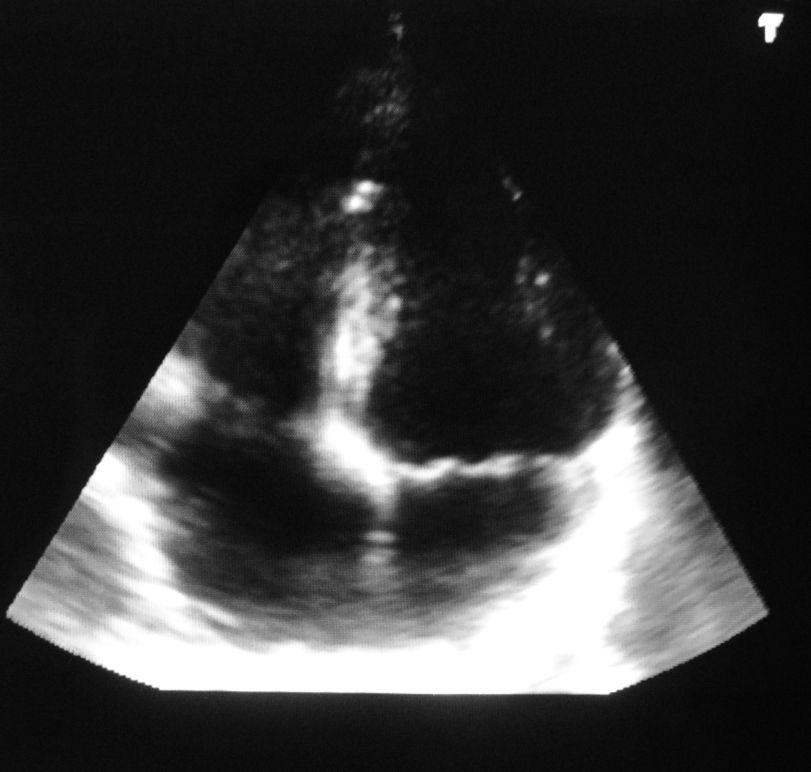

Sie sind hier: Gemeinschaftspraxis Benthake/Othman/Önder » Leistungen » tech. Untersuchungen » Echokardiografie